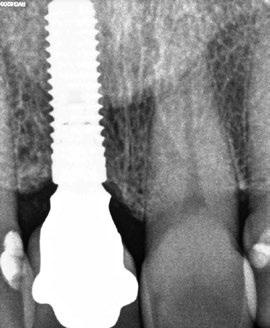

Egy fiatal páciens jelentkezett nálunk, akinek eltörött a szabad véggel rendelkező hídja (1. ábra). A hiányzó, első premoláris fog esetén implantációs pótlást javasoltunk. A csontállomány értékeléséhez CBCT-vizsgálatot végeztünk, és az elemzéséhez NNT Viewert (NewTom) használtunk, és copaSKY 4×10 mm-es (bredent medical) implantátumot választottuk a fog pótlásához

1. ábra: Műtét előtti fogászati panorámafelvétel, amelyen a hiányzó felső állcsont jobb első premolárisát és a szabad véggel rendelkező hidat láthatjuk. — 2. ábra: Az implantátum méreteinek megtervezése CBCT-vel. 3. ábra: Bukkális lágyrészdefektus. — 4. ábra: A biológiai szélesség értékelése a vertikális lágyszövetvastagság alapján. 5. ábra: Palatinális „tekercslebeny” – Palatal roll flap. — 6. ábra: Bredent medical copaSKY 4x10 implantátumbeültetés. 7. ábra: Szubkresztális implantátumbeültetés a várható biológiai szélességnek megfelelően.

(2. ábra). A lágyszövetek értékelése Seibert szerinti I. osztályú csontdefektust állapított meg (3. ábra), ezért a beavatkozáskor palatinális „tekercslebenyt” preparáltunk (palatal roll flap), és implantációt végeztünk, hogy kompenzálni tudjuk a bukkális lágyszövet-behúzódást. Megmértük a vertikális lágyszövetvastagságot, és úgy terveztük, hogy a szubkresztális implantátum beültetése összhangban legyen a biológiai szélesség kialakulásával a transzgingivális gyógyulási periódus alatt (4. ábra)

Az eljárást helyi érzéstelenítés mellett végeztük (4%-os articaine-hidroklorid 1:100 000 adrenalinnal). Papillakímélő, U alakú palatális bemetszést végeztünk, teljes vastagságú nyálkahártyalebeny preparálás történt, a lebenyt bukkálisan feltekertük (5. ábra). A lebeny bukkálisan feltekert részén de-epitelizációt végeztük el, amellyel kompenzálni tudtuk a bukkális lágyszöveti defektust. Szakaszos előfúrást végeztünk, és a bredent copaSKY 4x10 implantátumot 30 Ncm behajtási nyomatékkal helyeztük be (6. ábra). Az implantátumot 1 mm-re szubkresztálisan helyeztük be, hogy később szélesebb emergenciaprofilt tudjunk kialakítani (7. ábra). Az egyedi ínyformázó úgy készült, hogy kompozitot vittünk fel a titánbázisra, és így formáztuk a lágyszöveteket a transzgingivális gyógyulási fázis során (8. ábra). Az egyéni ínyformázó tulipán formájú, hogy kialakítsa a kívánt emergenciaprofilt. A lágyszövetet feszülésmentesen zártuk #6/0 nem felszívódó, monofil fonallal (Optilene, B. Braun Deutschland; 9. a–b. ábra). Posztoperatív röntgenfelvétel készült, ami alapján az implantátum a szomszédos fogakkal párhuzamos elhelyezést mutatott (10. ábra). Posztoperatív utasításokat adtunk a páciensnek a műtéti terület körüli szájhigiénia fenntartása érdekében. A beavatkozást követő egy héttel a varratokat eltávolítottuk, és a kezelt terület kielégítő gyógyulást mutatott (11. ábra). A 4 hónap utáni késleltetett terhelést a páciens kívánsága szerint terveztük.

10. ábra: A műtét utáni radiológiai felvétel.